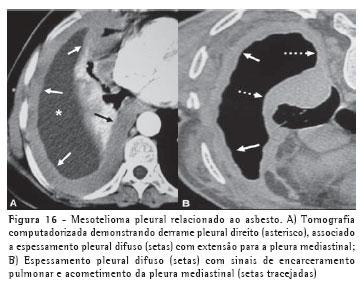

Apesar de haver descrições de mesotelioma em indivíduos com inflamação pleural crônica ou com história de exposição a carcinógenos químicos, a exposição ao asbesto está associada ao desenvolvimento do tumor em 50% a 80% dos casos. Dentre os achados radiológicos, o derrame pleural, geralmente unilateral, é o mais comum.

Podem também ser encontradas massas pleurais sólidas e espessamento pleural circunferencial com tendência a encarceramento pulmonar. A TC é o método de escolha na avaliação da presença e extensão do mesotelioma, apesar de os sinais não serem patognomônicos. Além destes achados descritos na radiografia, podemos encontrar espessamento irregular das fissuras, extensão para a pleura mediastinal, pericárdio e parede torácica e sinais de comprometimento à distância, como linfonodomegalias mediastinais, diafragmáticas e mamárias internas, e metástases linfáticas e hematogênicas (Figura 16).(21-22)